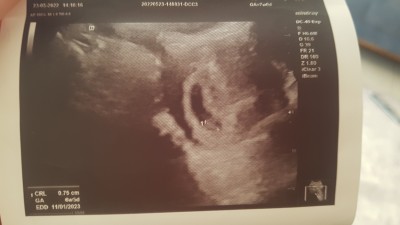

Cinsiyet tahmini tam 7 haftalık ters rahim demişti doktor

Kesesi erkek Bebek kesesine benziyo :)) sağlıklı gelsin kuzu

Daha sgliklimi değilmi eli kolu düzgün u o beli değil cinsiyeti nasıl belli olsun kız  ben bile 13 haftalığım daha ben bile ogrenemedim

Yoo çok erken değil. Kese şekline göre bebek erkek. Tahminlerim tutar.. Öğrendiğin zaman geç de olsa bu yorumun altına yaz canım.

az daha buyusun oyle getir annesi :) daha vitamin kiz bu